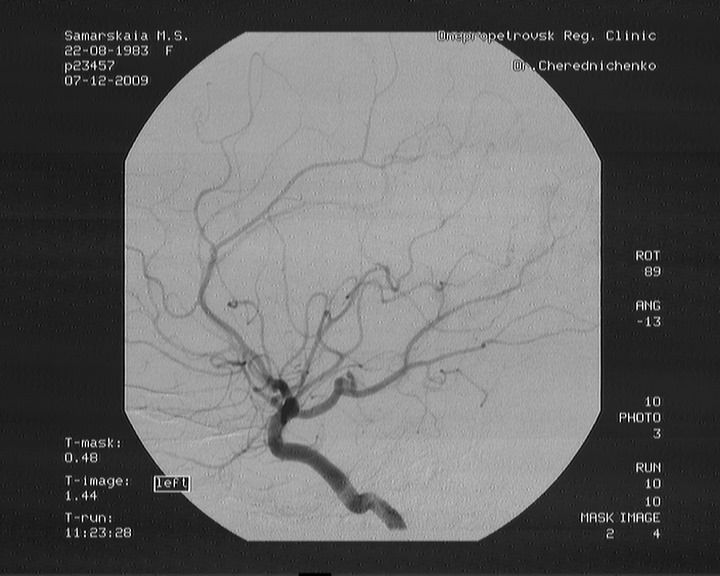

Некоторое время назад после обследования женщине был поставлен диагноз: артерио-венозная мальформация правой затылочной доли.

26 сентября была проведена частичная рентгенэндоваскулярная эмболизация в больнице им. Мечникова в Днепре. Было закрыто только 40 % мальформации. Сейчас женщина находится на реабилитации дома. Но через месяц ей требуется повторная госпитализация для проведения второго этапа эмболизации АВМ. На первую операцию было потрачено около 150 000 гривен и уже на вторую у женщины совсем нет средств. Марина Самарская обращается ко всем неравнодушным людям с просьбой о любой возможной помощи.